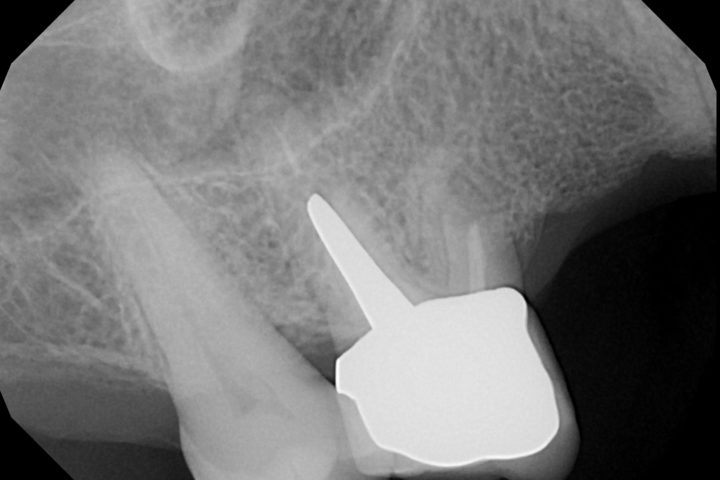

dopo

Radiografia – Prima e dopo apicectomia

L’immagine mostra il confronto radiografico tra la situazione iniziale, con evidenza di infezione all’apice radicolare, e il risultato post-operatorio dopo l’intervento di apicectomia: rimozione dell’area infetta e sigillatura della radice completata con successo.